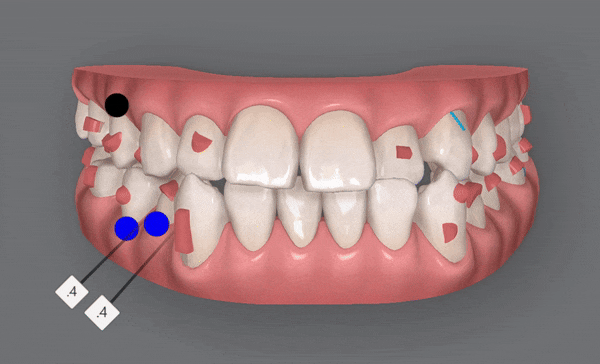

1st(46개)

첫번째 클린체크에서는 잠실교정치과 유펜바른치과에서 총 46개의 장치로

진행 해드렸습니다.

악궁이 점점 확장되면서 삐뚤빼뚤했던 치열들이 가지런하게 배열되고,

윗니 아랫니 사이의 공간이 점점 닫히며,

반대교합이 개선되면서 정상적인 교합으로

변하고 있는 모습을 확인해 보실 수 있습니다 ^^